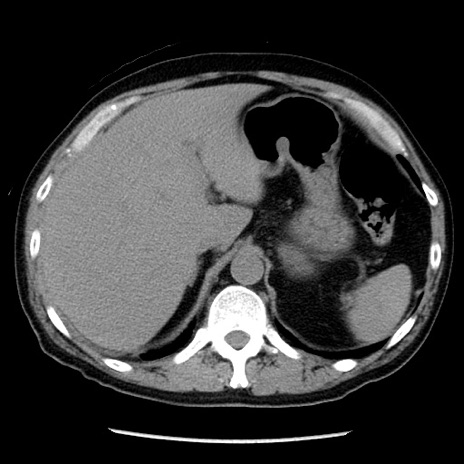

症例29(横断像)

【症例】40歳代男性

【現病歴】2日前から胃痛あり。徐々に周期的な激痛に変化した。本日になっても激痛があるため受診。

【身体所見】意識清明、BT 38-39℃台あり、腹部:膨満、やや硬、右下腹部に圧痛あり。

【データ】WBC 8500、CRP 23.26